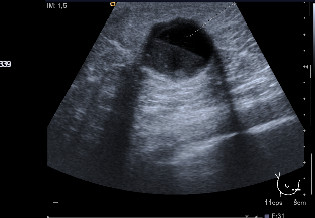

In a mammography of April 2009, a subareolar, oval-shaped, well-defined nodule of 16 mm with mammographic characteristics was observed: possibly benign (Birds 0). Extended studies were indicated through ecography of the left breast. The left breast ecography showed a well-defined cystic lesion in the left subareolar region with heterogeneous content, 19.1 x 12 x 17.8 mm that when compared with previous studies since 2006 showed an increase in size (Birads 4). The FNA evidenced a negative extension for malignant cells with findings consistent with the cystic content. With the above results ultrasound monitoring of the lesion after 3 months was decided upon. In the ultrasound of the left breast (July 2009) a cystic lesion was found with heterogeneous subareolar content of 12 x 8.4 x 12 mm (Fig. 1).

Figure 1

Well-defined cystic lesion with heterogeneous content